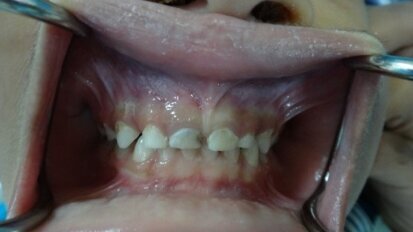

Avulsion in Paediatric Dentistry: Management of a Double Dental Emergency in a Child

General dental practitioners and paediatric dentists face real dental emergencies that effect children, especially dental trauma. Avulsion is considered, in...